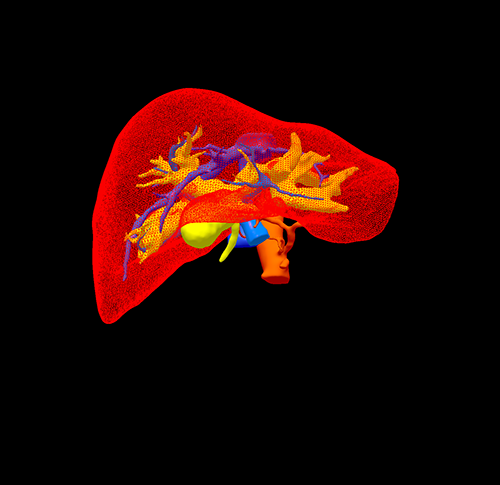

高位胆管癌-胆管癌根治(左半肝+尾状叶切除、右肝管胆肠吻合